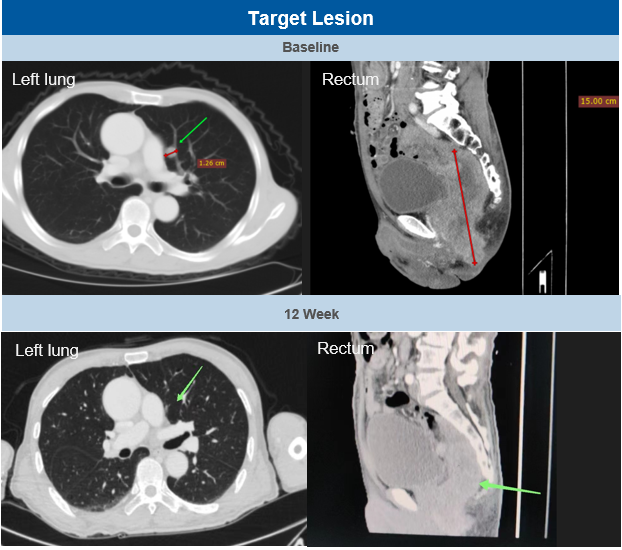

一位70岁亚洲男性黏膜黑色素瘤(mucosal melanoma)Ⅳ期患者在经过porustobart联合特瑞普利单抗每3周给药一次治疗后,在第6周时经历了非靶病灶“假进展”,在第12周及第18周时完善影像学检查均被评估为部分缓解(PR, partial response),靶病灶分别缩小64.2%和70.4%。该患者既往经过一线的帕博利珠单抗 + 达卡巴嗪 + 顺铂 + 贝伐珠单抗系统性治疗,因疾病进展停药,为抗PD-1抗体治疗失败的患者。